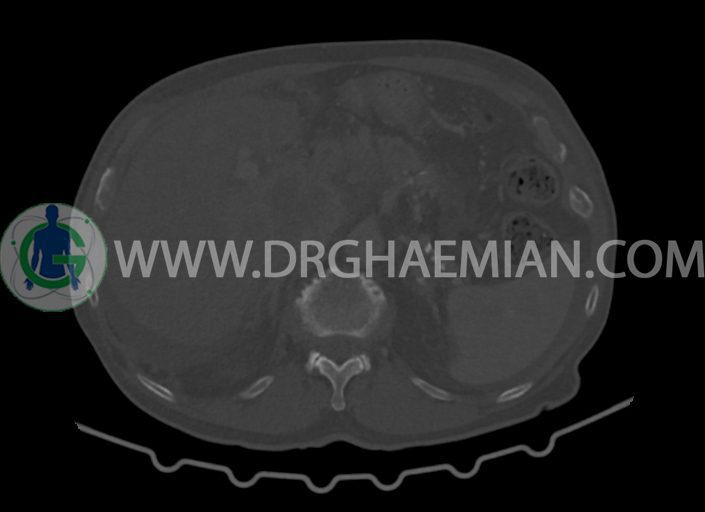

در سی تی اسکن اسپیرال شکم و لگن با کنتراست خوراکی و وریدی (مولتی دیدکتور 16 با مقاطع ظریف و بازسازی های ساژیتال و کرونال) :

ضایعه ای در کیسه صفرا، مجاری صفراوی، طحال، کلیه ها، پانکراس و آدرنالها مشهود نیست.

کلیه ها کنتراست را ترشح کرده اند و نمای سیستم پیلوکالیسیل و حالب دو طرف نرمال است .

ضایعه ای در معده و روده باریک مشهود نیست .

-مایع آسیت با حجم Mild در ساب فرنیک دو طرف ، ساب هپاتیک و ساب اسپلنیک و اینترلوپ لگنپ

-کیست های کورتیکال ساده در هر دو کلیه به بزرگترین قطر 27mm در سمت چپ (بوسنیاک 1)

-کلسیفیکاسیون آئورت شکمی و شاخه های آن

-توده ی بزرگ با حدود لبوله به ابعاد 89x87x76mm در لوب چپ کبد همراه با گسترش اکستراکپسولار و

شواهد آتروفی لوب جپ کبد

-توده به قطر 33mm در سگمان 6 کبد

-توده ی هیپودنس به ابعاد 30x21mm در ورید پورت خارج کبدی مطرح کننده ی Tumor thrombosis

در ارتباط با ضایعات کبدی در درجه ی اول متاستاز مطرح است. در تشخیص افتراقی با توجه به آتروفی لوب

چپ، mass forming cholangiocarcinoma نیز مطرح می گردد.